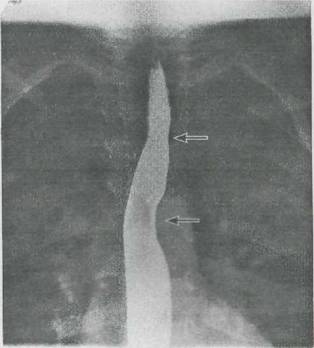

Fig. 9-8. Coarctatia aortei. Tranzitul baritat esofagian evidentiaza impresiuni esofagiene la doua niveluri (sagetile): nivelul superior (în dreptul coarctatiei) si nivelul inferior (prin dilatare poststenotica a aortei).